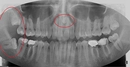

Diş ekimi, kaybedilen dişlerin yerine yapay dişlerin yerleştirilmesi işlemidir. Bu işlem, hem estetik hem de fonksiyonel açıdan birçok avantaj sunmaktadır. Diş ekimi, günümüzde diş hekimliği alanında en yaygın kullanılan yöntemlerden biri haline gelmiştir. Bu makalede, diş ekiminin faydaları detaylı bir şekilde ele alınacaktır. Diş Ekimi Nedir?Diş ekimi, kaybedilen dişlerin yerine cerrahi bir işlemle titanyum veya benzeri malzemelerden yapılan yapay diş köklerinin yerleştirilmesini içeren bir tedavi yöntemidir. Bu işlem, diş kaybının neden olduğu estetik kaygıları gidermenin yanı sıra, çiğneme fonksiyonunu da yeniden kazandırmaktadır. Diş Ekiminin Estetik FaydalarıDiş ekimi, hastaların gülümseme estetiğini önemli ölçüde iyileştirmektedir. Aşağıdaki avantajlar estetik açıdan dikkate değerdir:

Diş Ekimi SüreciDiş ekimi süreci, genellikle birkaç aşamadan oluşur: